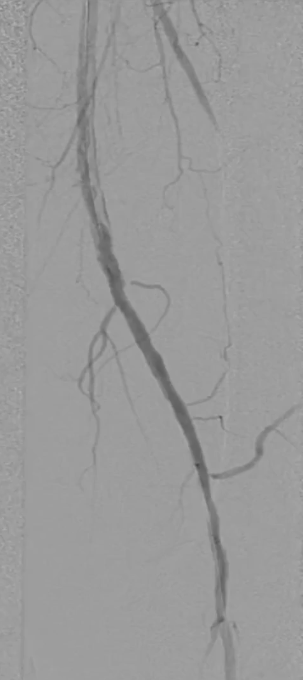

远端分支处理

造影发现颈前动脉疑似小血栓栓塞,尝试超选后用 3mm 普通球囊扩张,血流恢复(远端膝下三分之二流速尚可),因手术时间及患者配合度限制,未进一步处理。